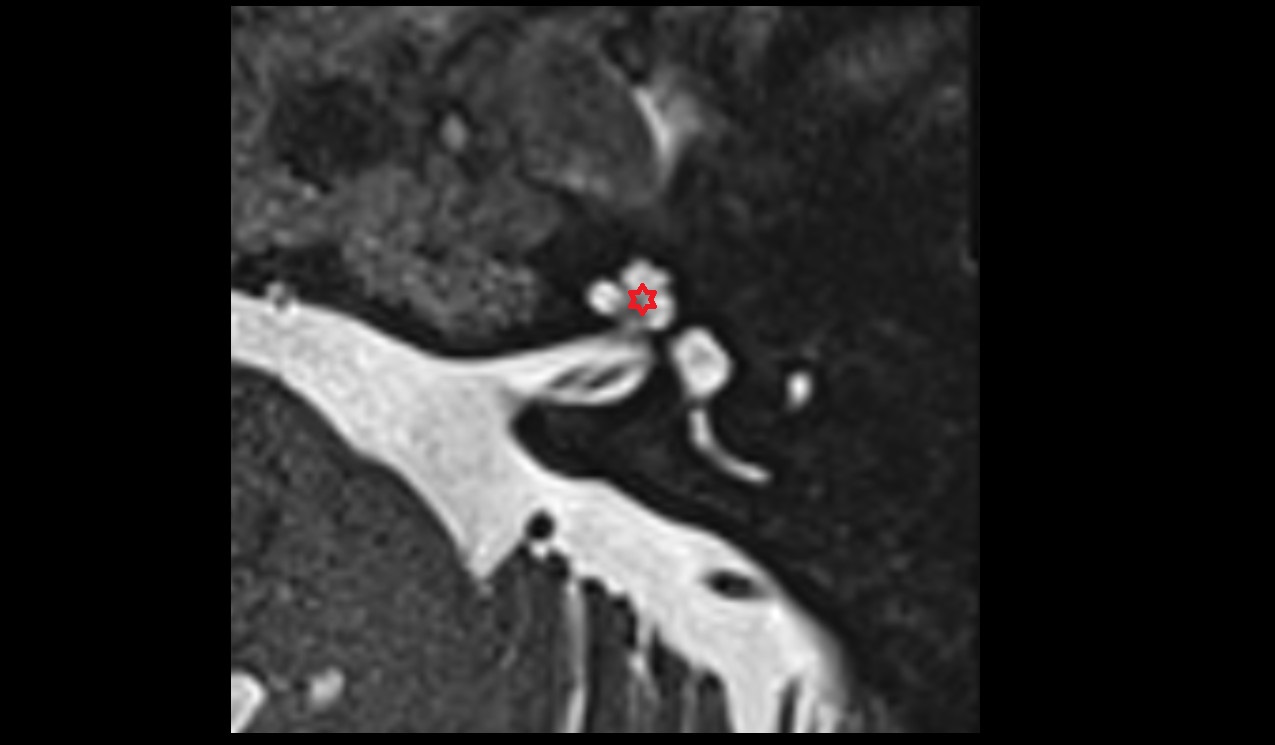

- Temporomandibular joint